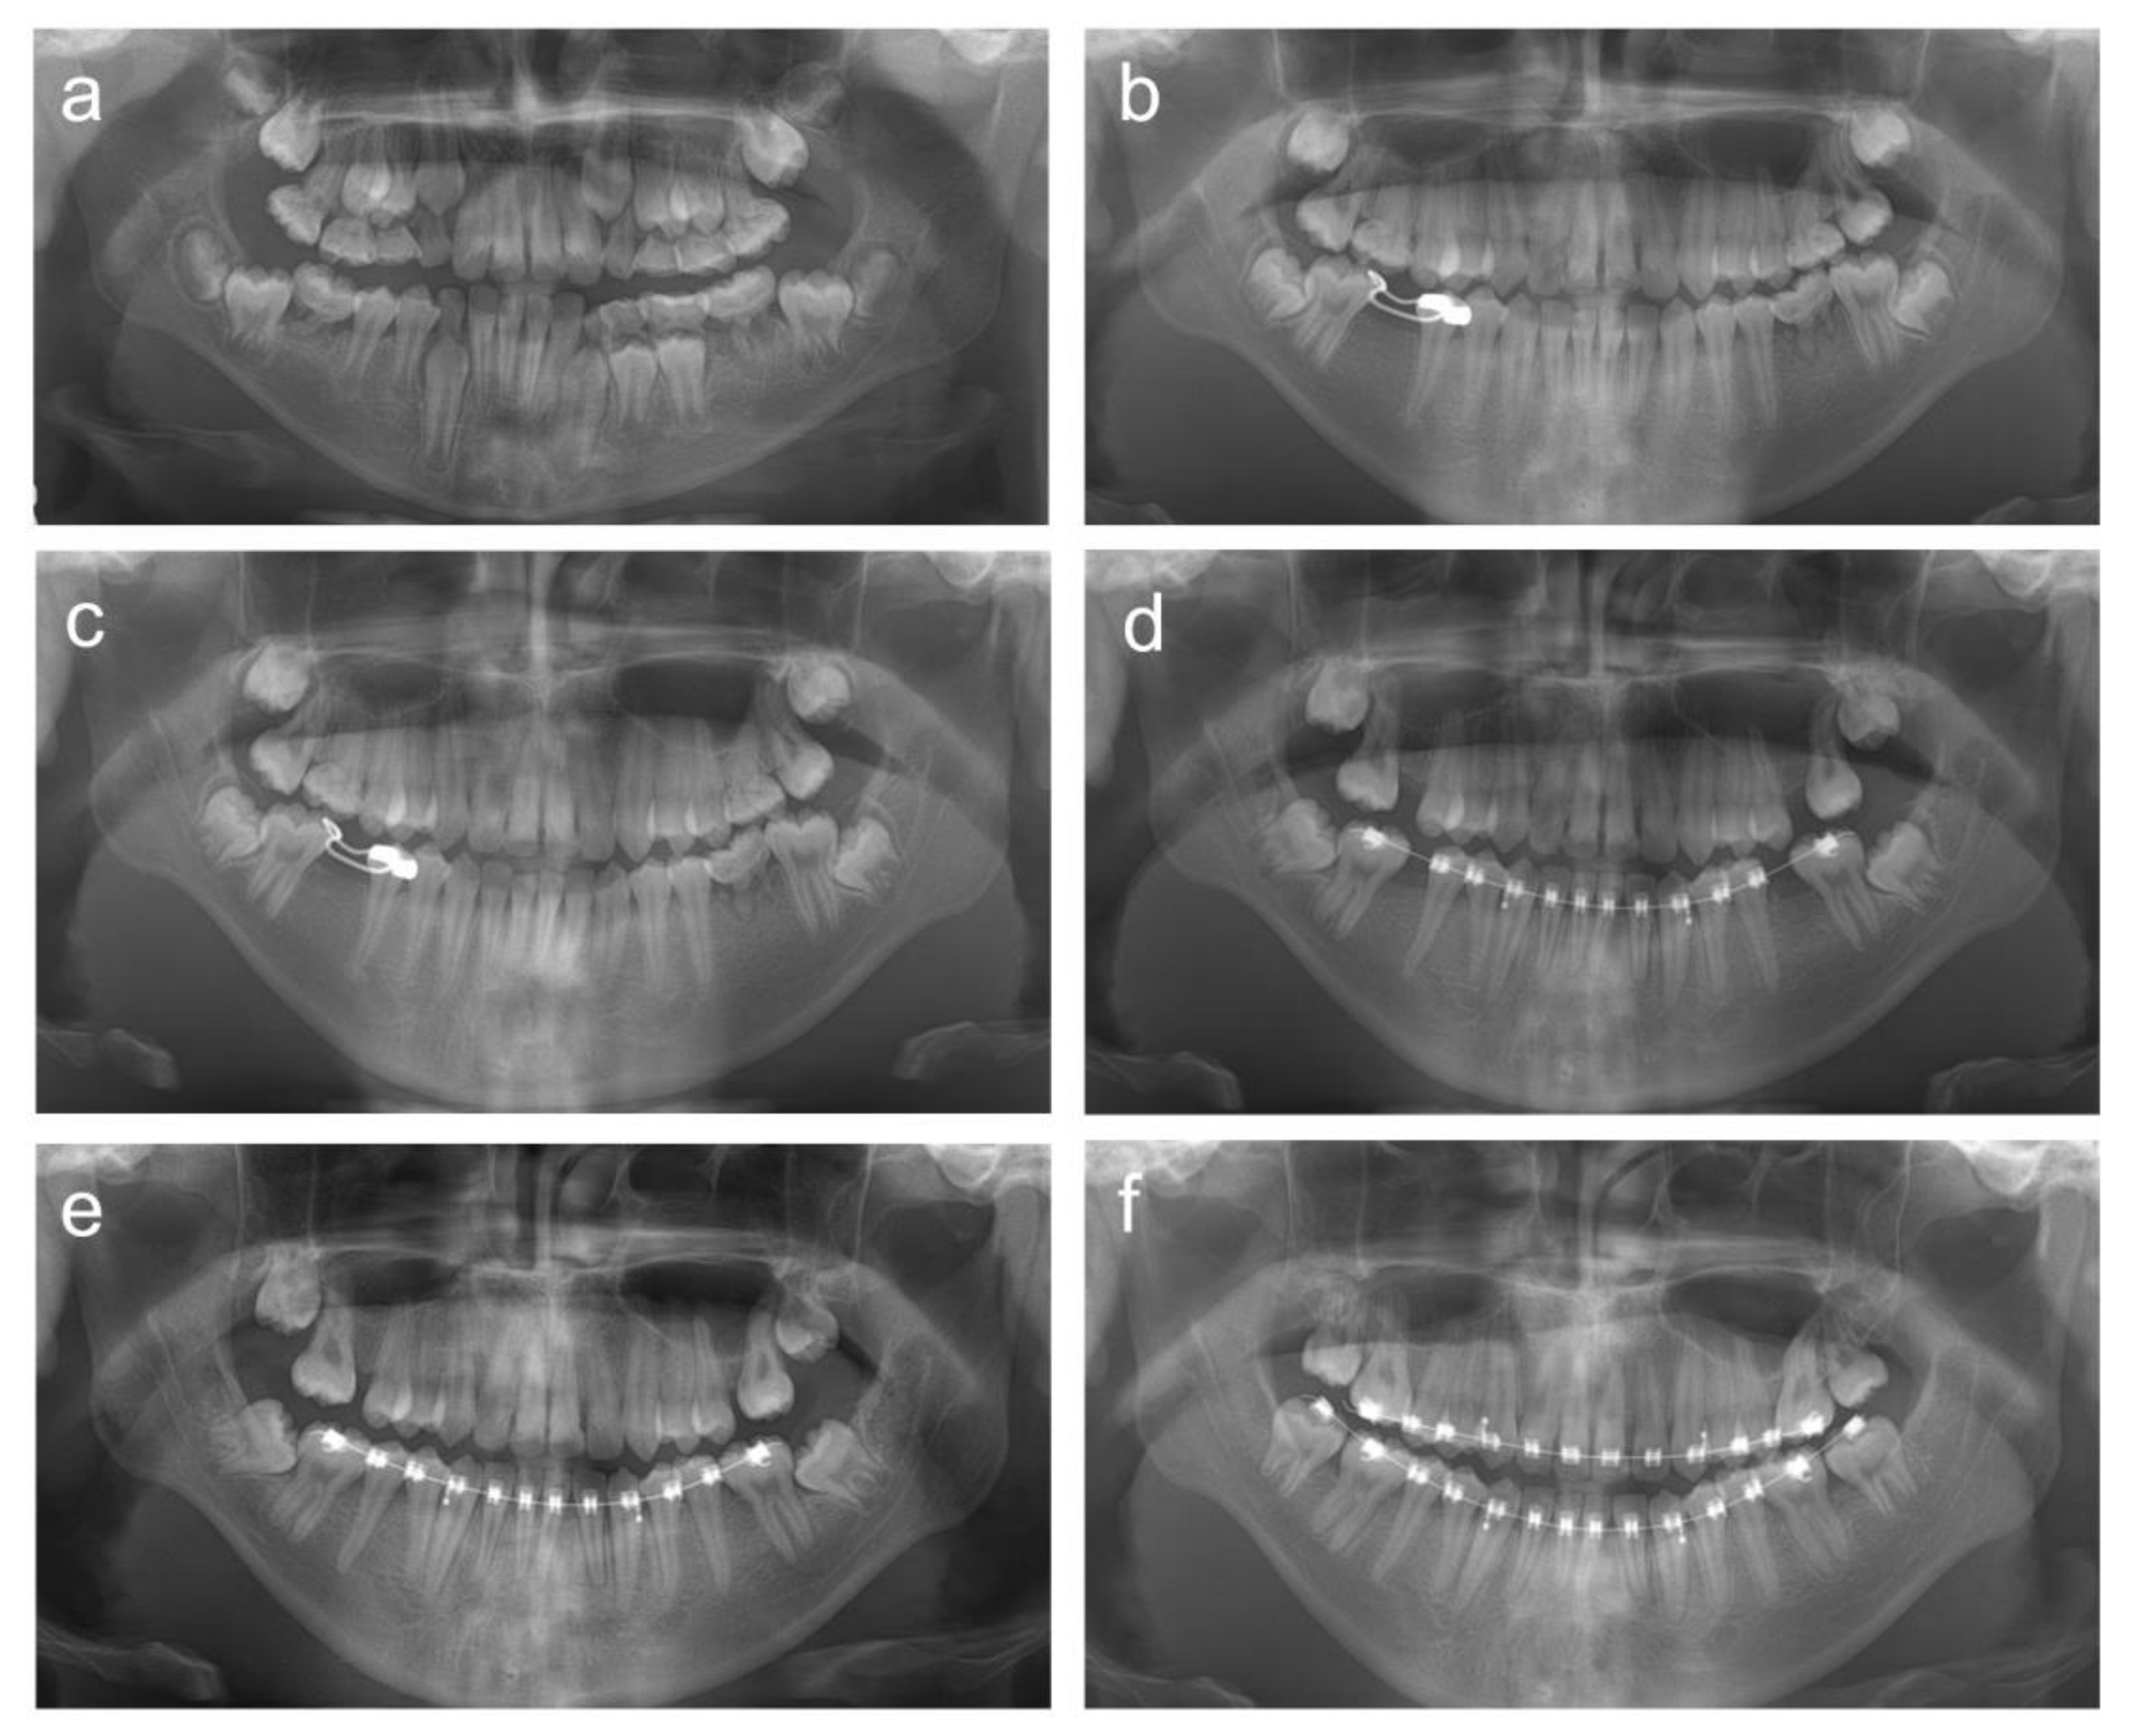

2.1. Case 1

2.2. Case 2

2.3. Case 3

2.4. Case 4

2.5. Case 5

3. Discussion